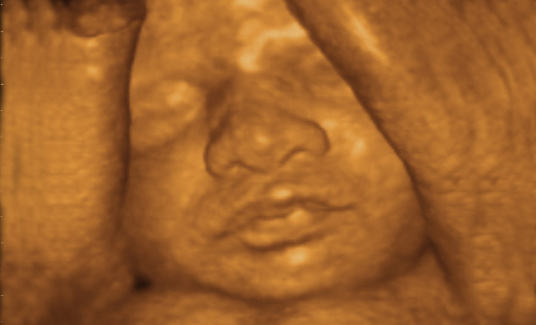

四维彩超是目前最先进的一种彩超技术,准妈妈可以清楚的观看到宝宝的动态图像。医生也能够根据四维彩超图了解宝宝的发育情况,是否有唇裂、脑积水、畸形等异常情况,方便医生和孕妇及早的采取应对措施;根据胎儿现今的发育情况及时补充营养,更有助于宝宝的身体发育和智力发育,提高宝宝的健康指数。